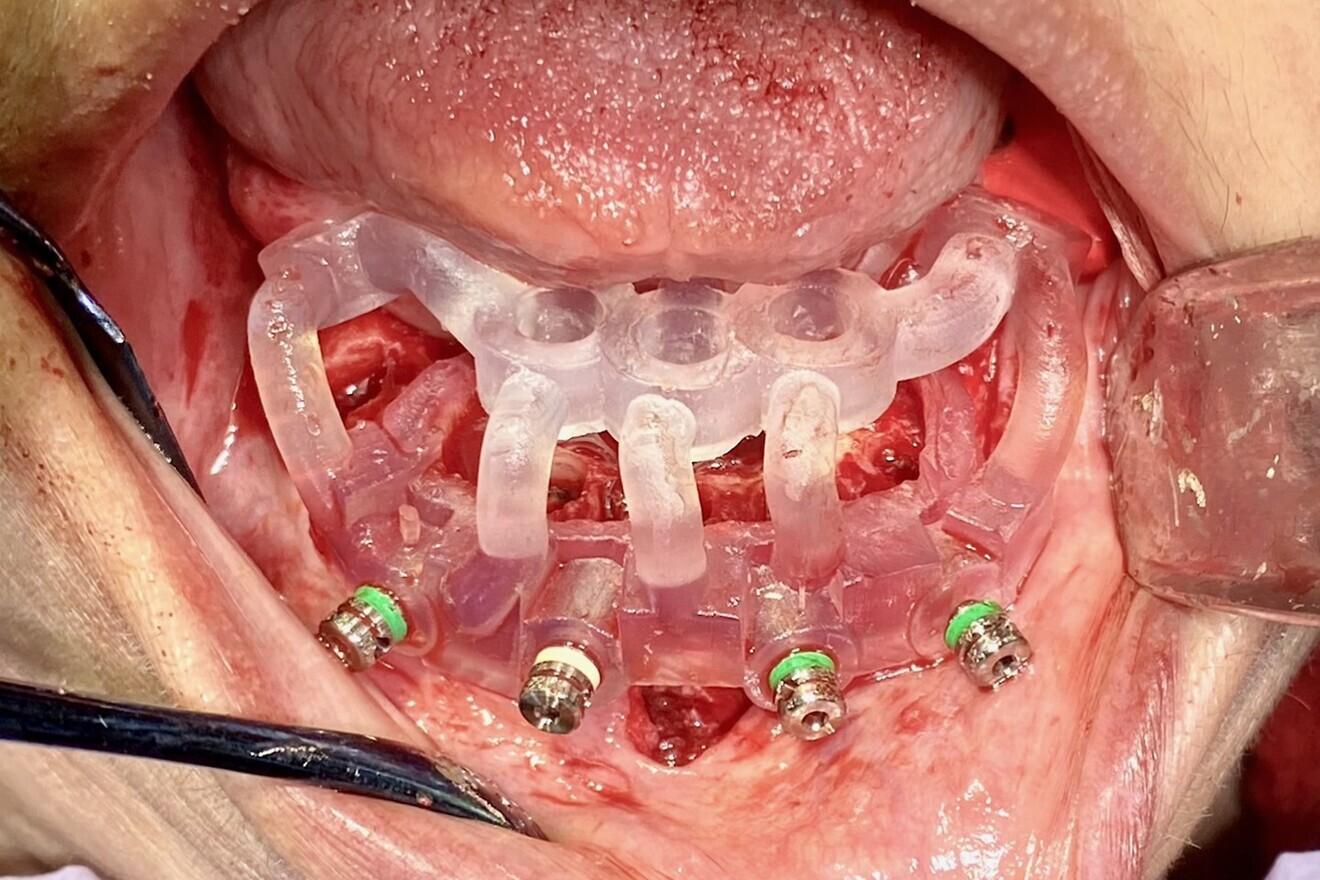

A full-thickness mucoperiosteal flap was elevated from the approximate areas of tooth #46 to tooth #35 and carefully reflected to expose the alveolar ridge. A bone reduction guide was placed over the site and fixated with four anchor pins. The bone was then reduced to the planned vertical height with rongeurs and flattened with carbide burs in a straight handpiece (Alveoplasty Kit, Meisinger USA). Based upon the 3D planning, the 3D-printed osteotomy drilling guide was designed to fit over the reduced bone and fixated in the same holes as the bone reduction guide (Fig. 13). The fixation pins were of two different lengths and secured the resin guide to the mandible (Fixation Kit, ROE Dental Laboratory). The osteotomies were prepared with sequential guided drills for accuracy, and five implants (Helix Grand Morse, Neodent) were placed approximately 2 mm subcrestally (Fig. 14). Although the implants all exhibited moderate insertion torque, the intermedullary bone density within the mandibular implant receptor sites was poor, as previously noted during the diagnostic phase.

Fig. 13: Surgical guide fixated to the mandible.